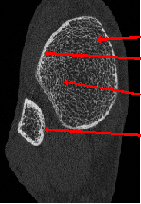

Case Report: Minimally Invasive Open Reduction and Internal Fixation of a Humeral Head-Splitting Fracture-Dislocation in A Young Man

Kyle Andrews1*, Ryan Sefcik2, Jacob Stirton1, Nabil Ebraheim1